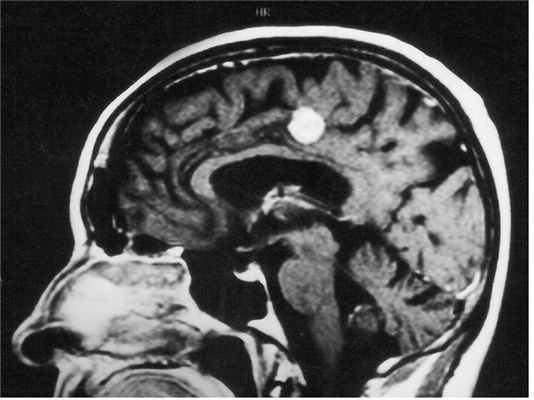

МРТ головного мозга. Менингиома свода черепа (стрелка). Аксиальная Т2-взвешенная МРТ.

МРТ головного мозга. Менингиома серпа. Аксиальная и корональная Т1-взвешенные МРТ с контрастированием.

При МРТ головного мозга выявляется образование с широким основанием. Гиперостоз, часто видимый при КТ и на рентгенограммах, при МРТ головного мозга выглядит как утолщение внутренней костной пластинки свода черепа. Кальцинаты, обнаруживаемые при КТ в 20% наблюдений, при МРТ не видны. Опухоль при МРТ довольно однородная по структуре. Прорастание костей свода черепа видно отчетливо как участок повышенного сигнала на МРТ головного мозга любого типа в резко гипоинтенсивной кости. Сигнал от опухолевого узла на Т2-зависимых МРТ зависит от гистологического подтипа: относительно низкой интенсивности (между белым и серым веществом) при фибробластном и высокой при ангиобластном и синтициальном. Отек выражен в различной степени в каждом конкретном случае. Ряд МРТ признаков очень характерен для менингиомы: полоса ликвора между опухолью и тканью мозга, смещение окружающих сосудов. Они отражают неинвазивный характер роста. Смещенную и вовлеченную твердую мозговую оболочку иногда удается визуализировать при МРТ после введения гадолиния, особенно на корональных МРТ срезах. Усиление сигнала при МРТ с контрастированием от оболочки над опухолью с распространением в стороны (симптом “хвоста”) не абсолютно специфично и встречается при МРТ как при менингиоме, так и при лептоменингиальных метастазах. Однако при глиальных опухолях и невриноме при МРТ оно не описано. При обследовании пациентов методом МРТ в СПб с менингиомами серпа (фалькс-менингиомы) и намёта мозжечка рекомендуется делать МР-венографию для определения компрессии синуса и его проходимости. В наших центрах это обязательное исследование перед операцией. На открытом МРТ венография также легко выполнима. Не все центры МРТ СПб придерживаются этой методики.